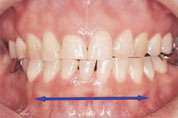

- ATTRITION

- 歯の咬耗(こうもう)

- 下顎前歯の咬耗